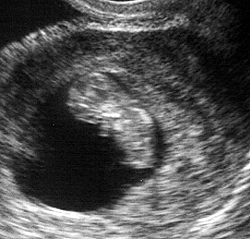

الأسبوع التاسع:

ينتقل الآن مولدك في المستقبل إلي مرحلة مختلفة في النمو حيث يختلف اسمه الآن وينتقل من مجرد حميل إلي جنين كما يسمى في الأغلب. يبدأ الرحم في الاتساع ليشتمل علي منطقة أوسع وأكبر، وينمو الجنين أكثر ويصبح حوالي 2.5 سم طولاً . تحدث تغيرات كثيرة للجنين من عضلات وأعصاب للقيام بوظائفها، تبدأ اليد في التثبت بالمعصم وتبدأ الجفون في تغطية منطقة العين. تظهر أيضاً مع بداية هذا الأسبوع تغيرات جسمانية علي السيدة كالتي تظهر في بداية الحمل حيث يتضخم الثدي بشكل أكبر ويتسع محيط الخصر.